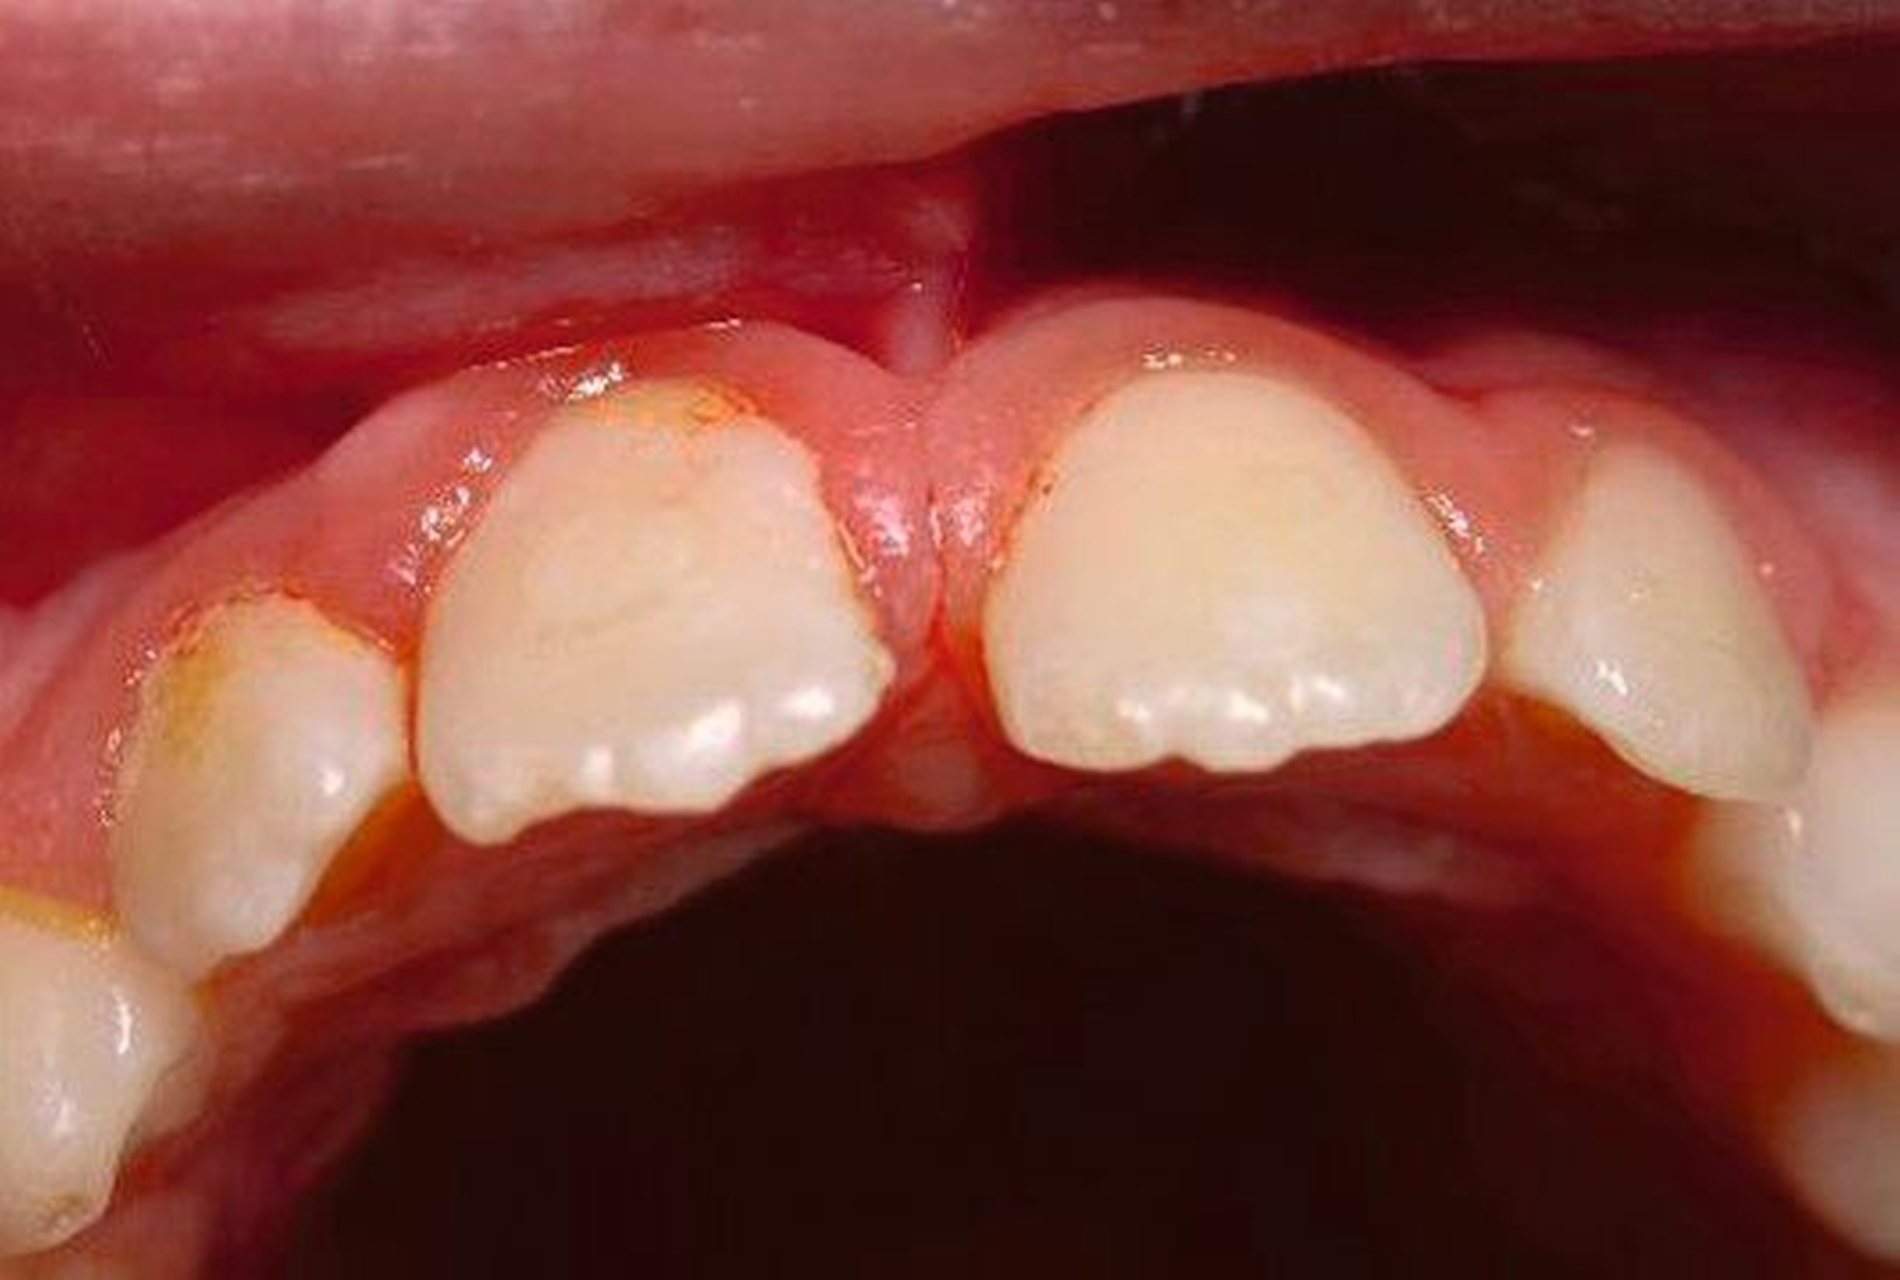

Abbildung 4 zeigt eine Milchzahn-Transplantation im frühen Wechselgebiss bei einem achtjährigen Mädchen bei nahezu vollständiger Ersatzresorption des Zahnes 11 nach Avulsion und Replantation. Trotz des sehr guten Zustands des Milchzahntransplants im Alter von zwölf Jahren entschied man sich in Rücksprache mit den Kollegen der Kieferorthopädie für die Prämolaren-Transplantation als eine zuverlässige Versorgung mit Überlebensraten von im Mittel 96,7 Prozent nach 8,75 Jahren [Akhlef et al., 2017]. Die Planung der Prämolaren-Transplantation sollte dabei immer in enger Absprache mit der Kieferorthopädie erfolgen, um zu klären, ob die Entnahme eines Prämolaren vertretbar und welche Entnahmestelle die geeignetste ist.